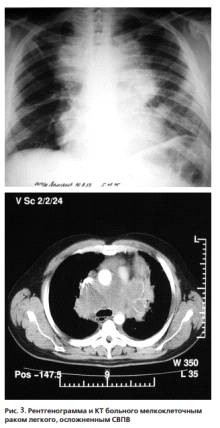

Необходимо отметить, что СВПВ чаще встречается при мелкоклеточном раке легкого,

чем при других морфологических формах. На втором месте - плоскоклеточный